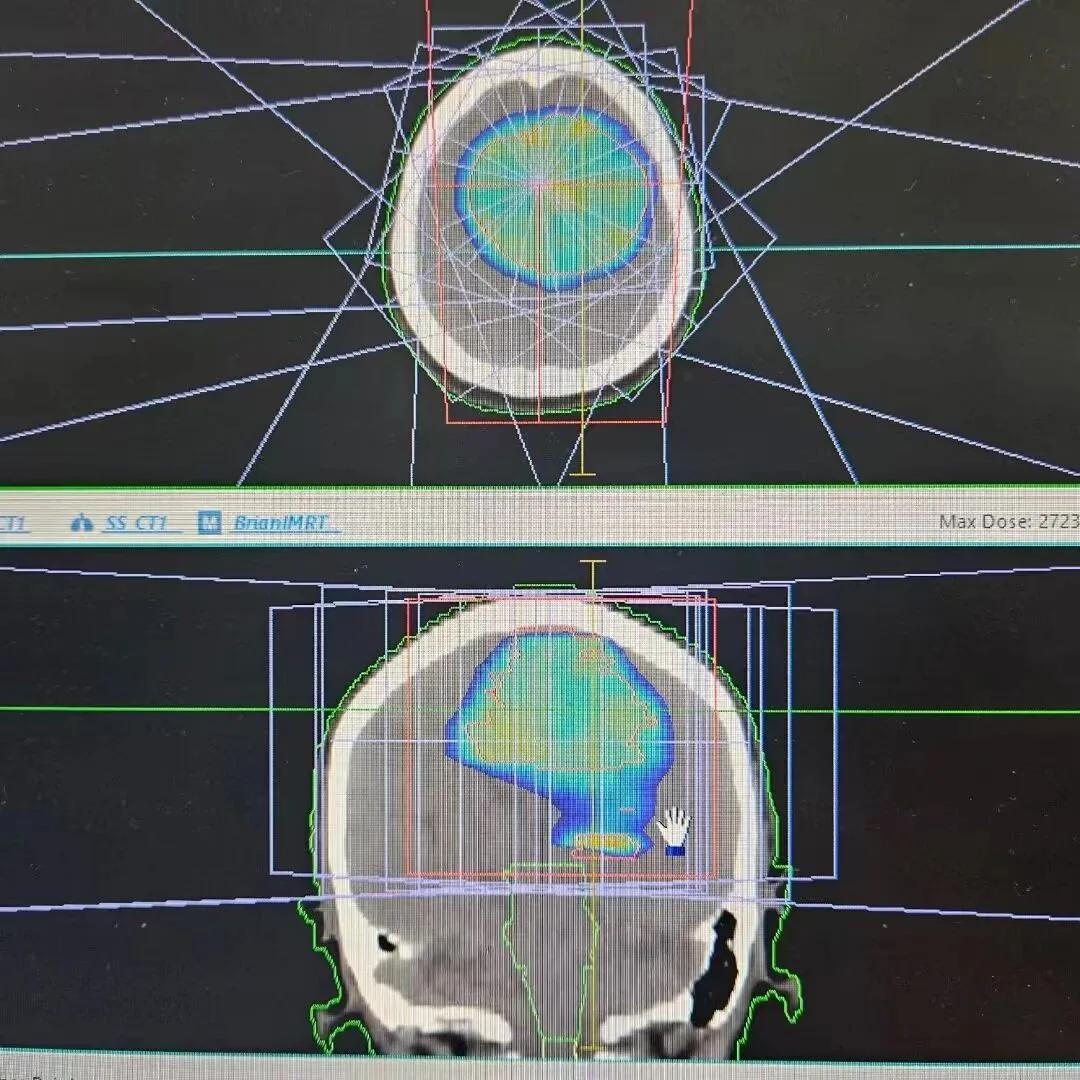

入院后,肿瘤科贺选主任团队第一时间为患者完善各项相关检查,全面评估病情,为患者量身定制了个性化治疗方案——采用适型调强放射治疗,同时辅以全程营养支持与心理护理干预。